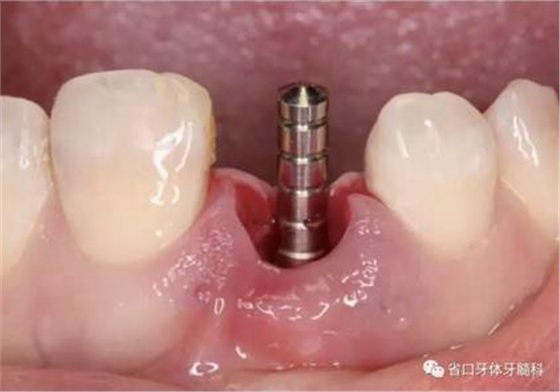

(1)微創(chuàng)拔牙及即刻種植:術(shù)前拍攝口內(nèi)照及實(shí)施牙周基礎(chǔ)治療。常 規(guī)消毒鋪巾阿替卡因局麻下微創(chuàng)拔除上頜右側(cè)中切牙,搔刮拔牙窩及根尖肉 芽組織。探測牙槽骨唇側(cè)骨壁及鄰面牙槽嵴完整,牙齦無撕裂。不翻瓣下于上頜右側(cè)中切牙缺隙近遠(yuǎn)中中點(diǎn)的腭側(cè)牙槽骨及根方定位,按照逐級預(yù)備的原則,緊貼牙槽窩腭側(cè)骨壁制備種植窩洞,植入Zimer®3.7mm×13mm TSV種植體1顆,植入扭矩>35N·cm,以O(shè)sstell測量種植體的ISQ值為68。 種植體平臺位于唇側(cè)齦緣中點(diǎn)下3mm,與唇側(cè)骨壁內(nèi)側(cè)面形成的跳躍間 隙約2mm,置入Bio-Oss®細(xì)顆粒骨粉0.25g,上愈合基臺關(guān)閉創(chuàng)口。術(shù)后 CBCT檢查顯示:種植體利用牙槽窩根方骨質(zhì)固位,緊貼牙槽窩腭側(cè)骨壁, 其唇側(cè)面與牙槽窩唇側(cè)骨壁的內(nèi)側(cè)面所形成的跳躍間隙(約2mm)可見顆 粒狀顯影物充填。牙槽窩的唇側(cè)骨壁及唇側(cè)倒凹無缺損穿孔。

圖15 植入種植體并置入覆蓋螺絲

圖16 跳躍間隙植骨

圖17 跳躍間隙植骨

圖18 測量ISQ值

(2)制備臨時冠:術(shù)后當(dāng)天取模轉(zhuǎn)移,送工廠以Zimmer®多功能 攜帶體為臨時基臺制備臨時修復(fù),獲得舌隆突開孔螺絲固位的烤塑臨時 冠。將其就位于口內(nèi)種植體,調(diào)整正中、前伸及側(cè)方咬合無接觸,加力 10~15N·cm,可見即刻修復(fù)體良好地支持齦緣及牙齦乳頭結(jié)構(gòu)。

圖21 烤塑臨時冠

圖22 臨時冠就位前袖口檢查

圖23 就位臨時冠